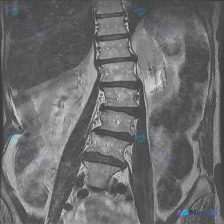

整理到一份腰椎MRI T1加权冠状位的影像资料,先放核心观察点,大家第一眼会怎么考虑? 影像核心表现(仅基于提供的T1序列): 1. 脊柱力线:明显腰椎侧凸,向右侧弯 2. 椎间隙:下腰椎(L4-L5、L5-S1为主)不对称变窄,凹侧(左侧)更明显 3. 椎体:边缘可见骨质增生(骨赘) 4. 骨髓信...